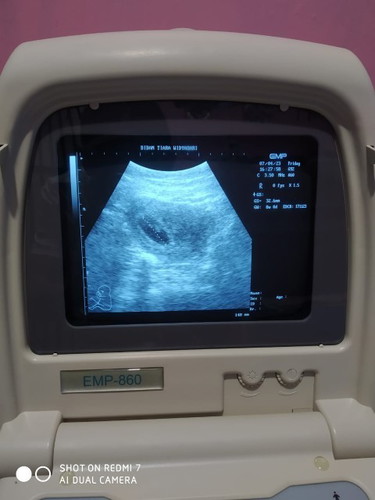

Usia berapa ya bun baru terdengar detak jantung janin? )kemarin sya USG usia 8 week

Tapi belum terdengar djj nya